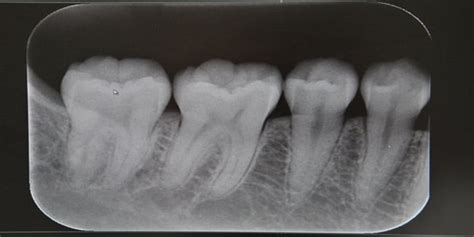

Exploración Radiográfica:

Se le realizó la exploración radiográfica de la cual os presento la ortopantomografía y la radiografía periapical.

- ¿Cuál ha sido el motivo del fracaso que se presenta en la RX periapical?

Radiografía periapical